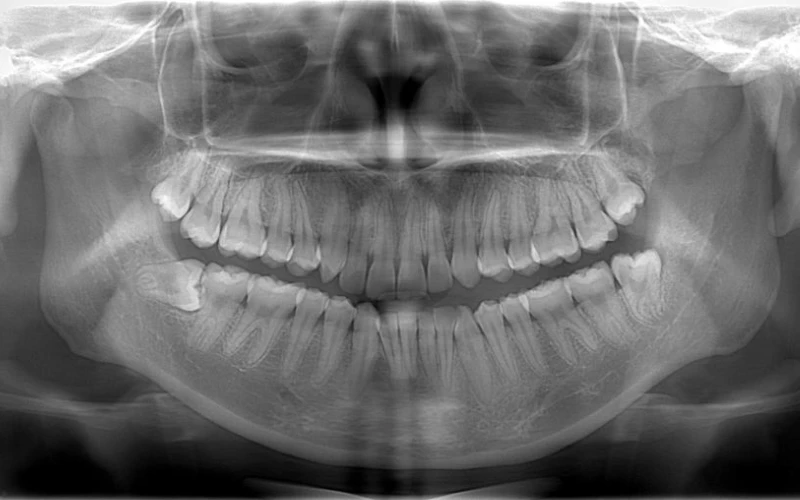

Trong trường hợp khác, khi có trong tay tấm phim nha khoa toàn cảnh của bệnh nhân, “công cụ” này cũng cần đạt đến độ sắc nét nhất định mới có thể bộc lộ được những vấn đề mà bệnh nhân đang gặp phải.

So với phim cận chóp chỉ khu trú từ 3-4 răng, bạn sẽ nhìn rõ những bệnh lý tồn tại ở những chiếc răng đó. Nhưng điều đó không chắc rằng mọi chiếc răng khác đều khỏe mạnh.

Đúng là “khó mà làm dâu thiên hạ”, nhưng sự thật là những điều tiêu cực họ sẽ nhớ lâu hơn là cảm giác thoải mái và dứt cơn đau sau điều trị. Thế nên mới cần đến X-quang toàn hàm! Bởi sau khi bạn có trên tay tấm phim này, những vấn đề của bệnh nhân sẽ được bộc lộ tất thảy. Họ sẽ bị thuyết phục bởi một tấm phim X-quang toàn cảnh sắc nét và chấp nhận điều trị một cách dễ dàng.